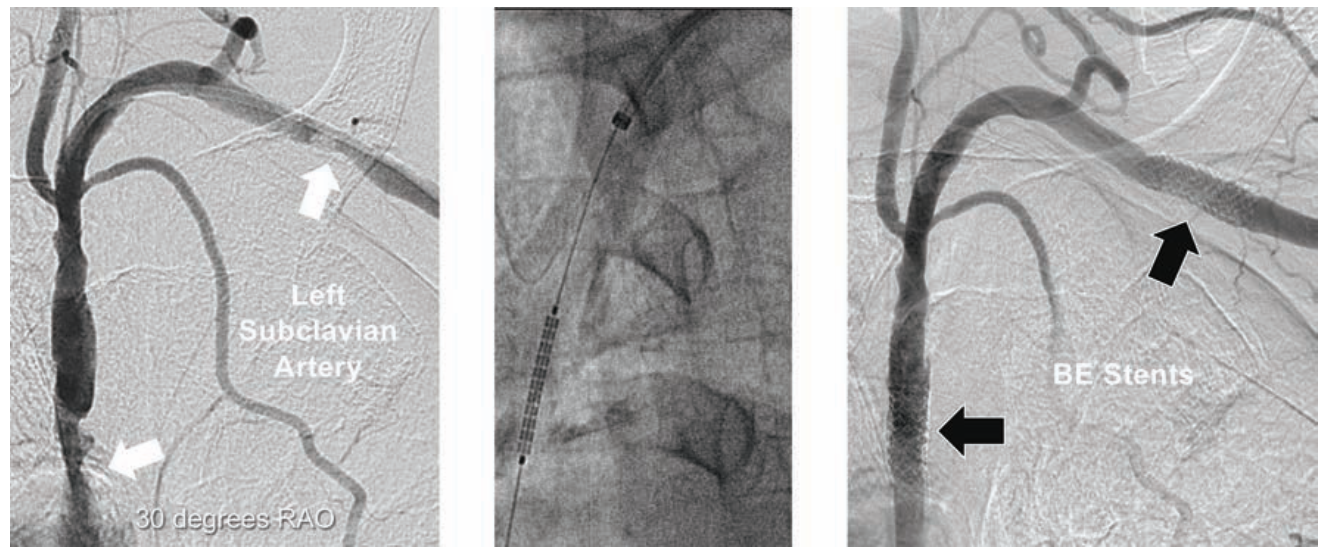

Case #7

A 70-year-old female with severe left arm claudication and no palpable left arm pulses underwent angiography using 5 Fr left TRA (Figure 7). The 5 Fr access sheath was exchanged over an .035-inch 260 cm Wholey guidewire advanced to the aortic root for a 5 Fr 90 cm Flexor Shuttle sheath, with guidewire exchange for a 180 cm coronary .014-inch guidewire. The two left subclavian lesions were pre-dilated with a Viatrac 6 mm x 15 mm RX PTA balloon, followed by a Herculink Elite RX 7 mm x 18 mm BE stent at the ostium, and a Herculink Elite RX 7 mm x 15 mm BE stent in the mid segment. Use of a TR Band allowed hospital discharge in 3 hours. The patient had immediate and sustained relief of her arm claudication.

Tips and Tricks for 5 Fr Subclavian Artery Stenting

The patient had no palpable left radial pulse. Ultrasound guidance allowed recognition and sizing of her small radial artery, and facilitated initial access for sheath placement. Contrast injections via the 5 Fr guiding sheath allowed accurate deployment of the Herculink Elite RX BE stents in the ostium and mid segment of the left subclavian artery.